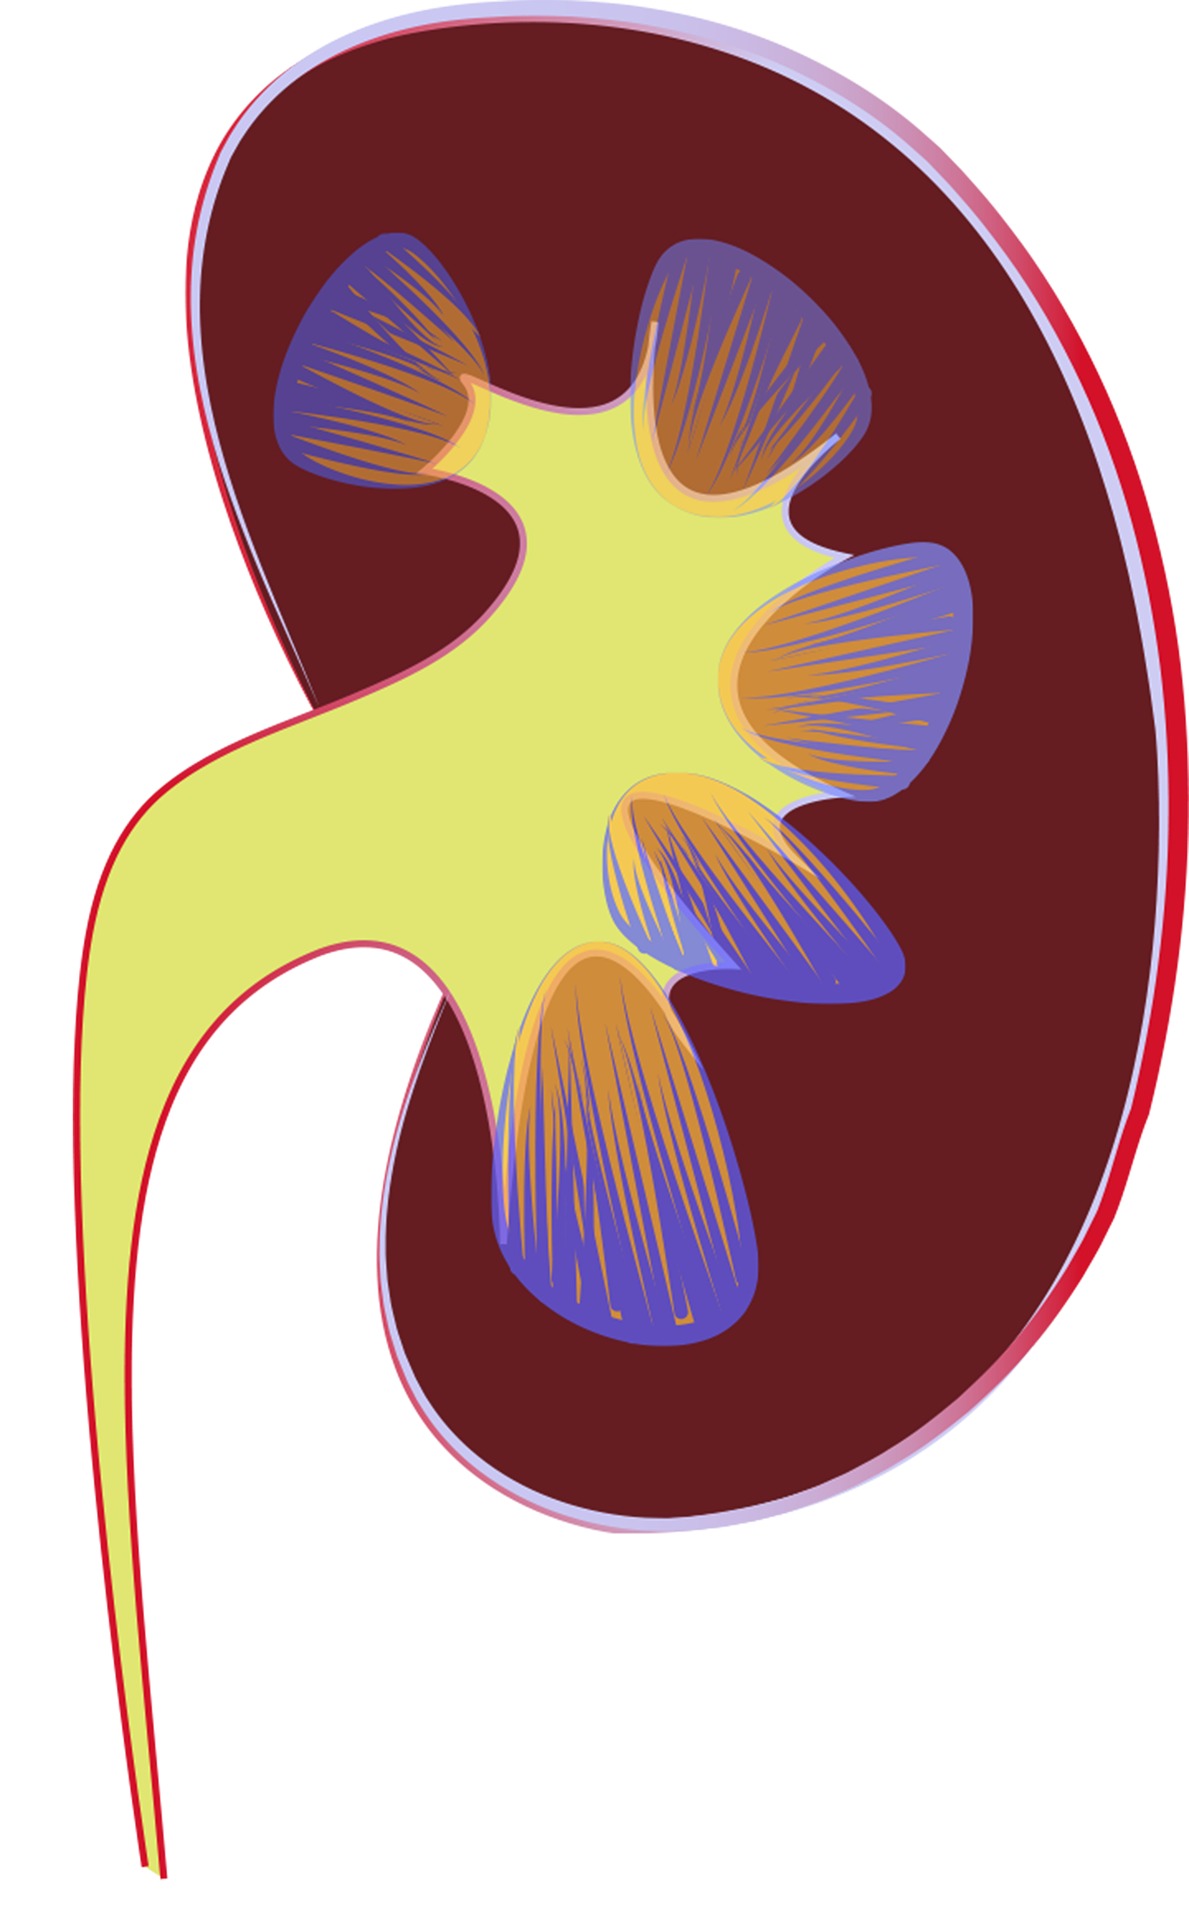

Conversamos con el Dr. Luis Hernández Mendoza médico nefrólogo con especialidad en trasplante renal, jefe de consulta postrasplante en el Hospital Universitario de Caracas y en la Clínica Sanatrix, sobre la deficiencia renal.